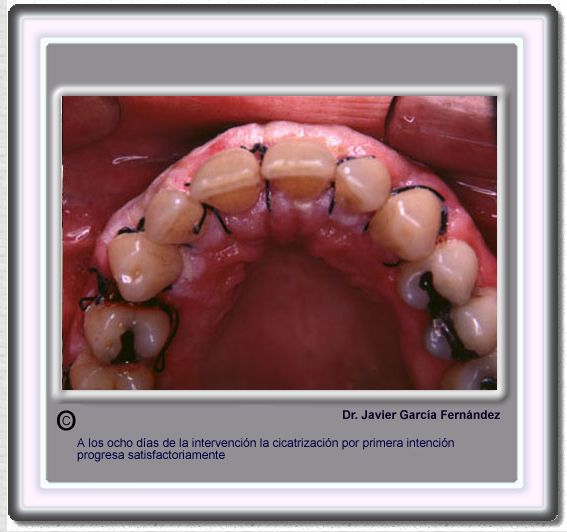

image 156